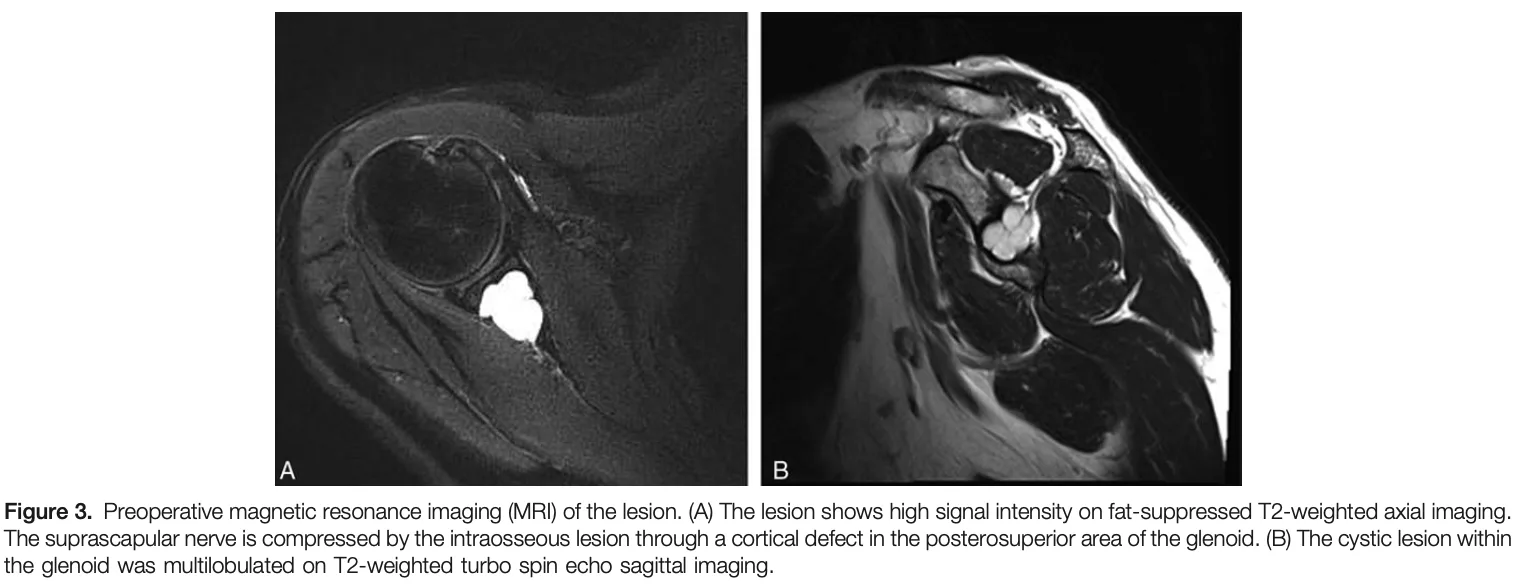

肩甲骨関節窩部にT2強調画像で液体の貯留を示す白く写る病変が認められます.

MRIでは液体貯留を示唆する所見があり, 骨内ガングリオンが疑われましたが, 軟骨性腫瘍を否定するため, 造影MRIを撮像し直すことにしました.

病変は周辺部のみが造影され, 内部には造影効果を認めず, 嚢腫性病変と判断.

骨内ガングリオンの診断が確定しました.